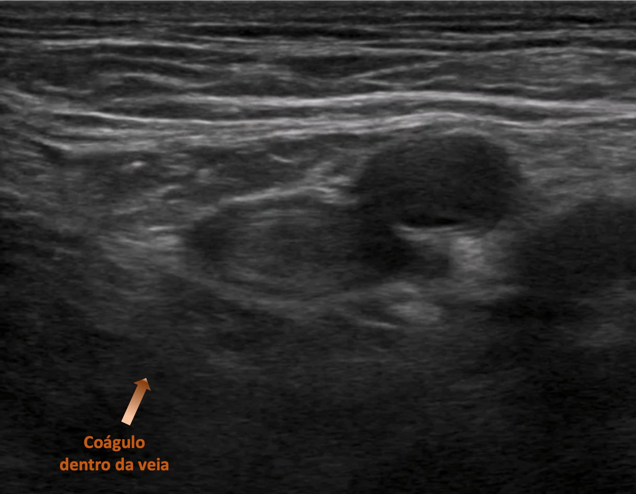

É uma doença que decorre da formação de coágulos ( trombos ) dentro das veias profundas, causando seu entupimento parcial ou total, acarretando em sérias consequências na vida das pessoas. Pode acometer qualquer veia do corpo porém 90% dos casos ocorre em veias dos membros inferiores.

O diagnóstico na maioria das vezes é feito pelo exame médico vascular detalhado e pode ser complementado com ultrassom doppler venoso do seguimento acometido que confirma a doença, entre outros critérios, pela ausência de fluxo em um segmento do vaso.